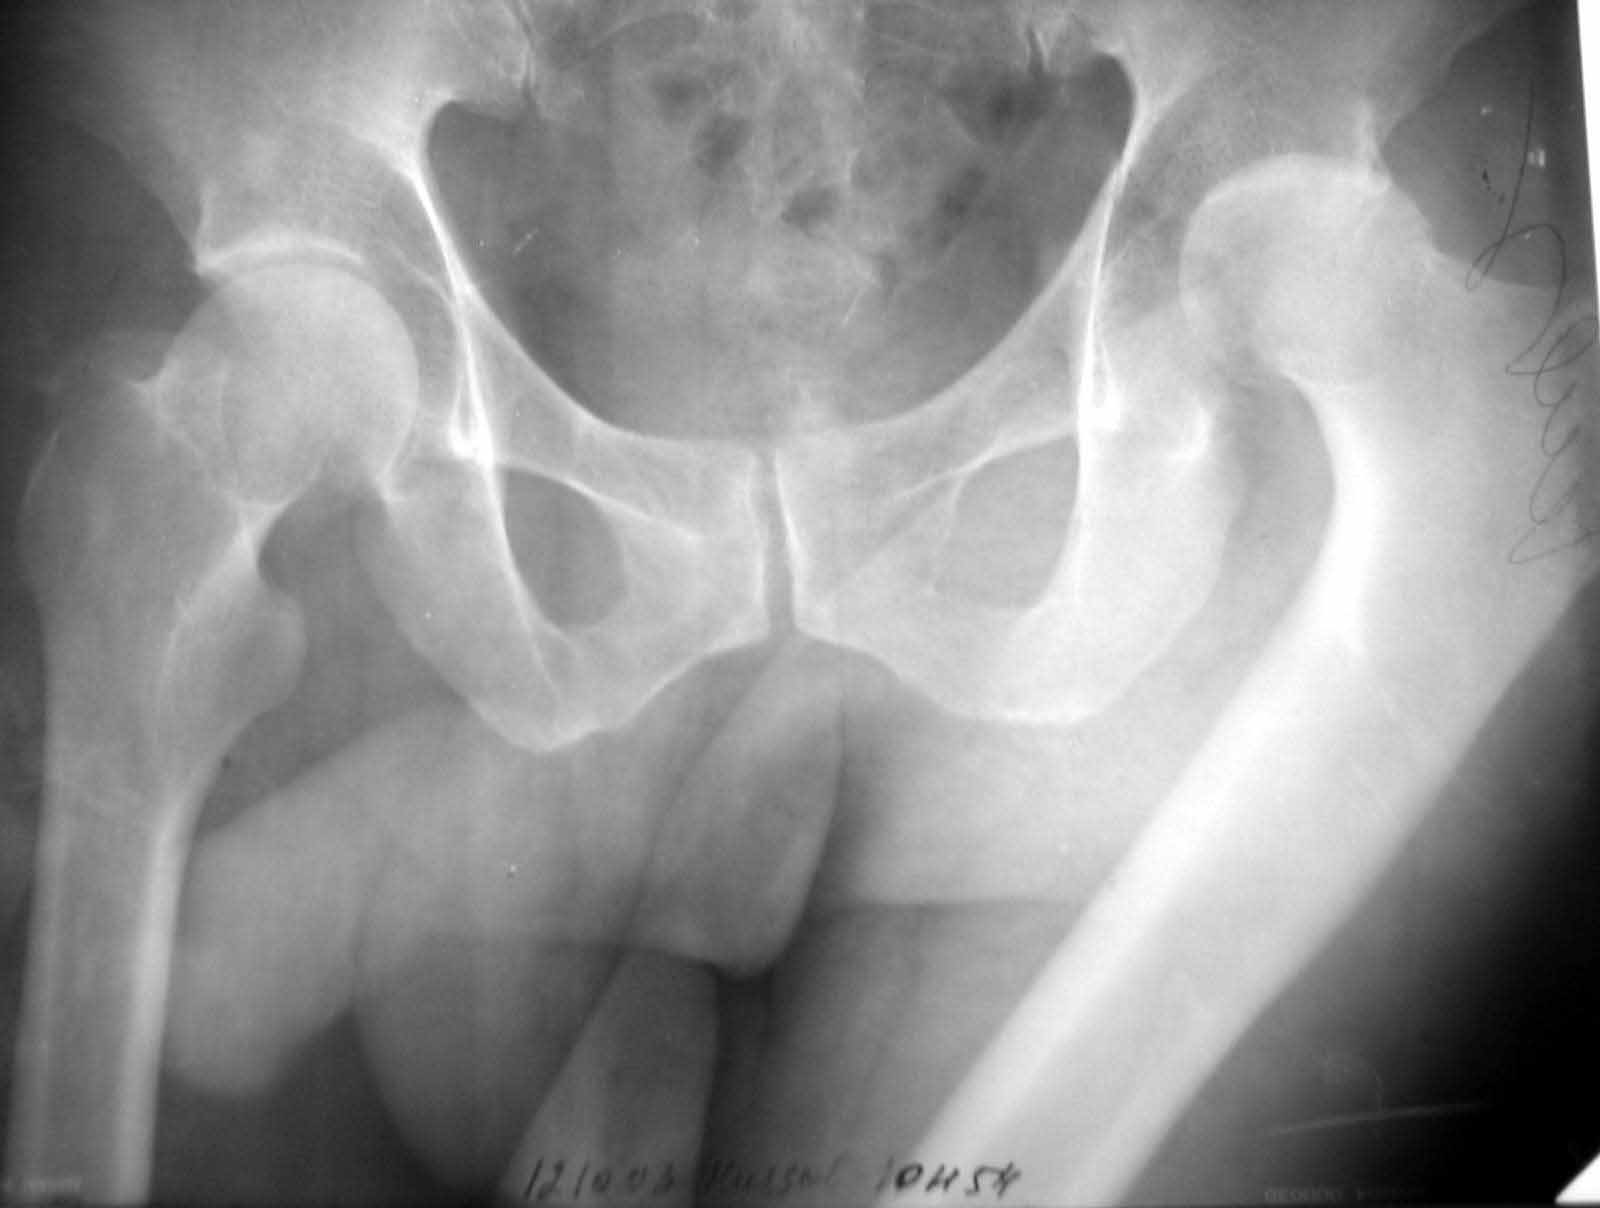

Больной Н. 54 лет. Поступил в подвздошным вывихом левого бедра. После попытки закрытого одномомендного вправления 2 мес. на скелетном вытяжении. На Rg контроле видимость вправления, на КТ - неустраненный вывих. По причине тяжелой соматической патологии открытое вправление и репозицию заднего края выполнить не представляется возможным. Вправление аппаратом внешней фиксации, КТ - этапах вправления - дефект заднего края. Что вы нам посоветуете по дальнейшей тактике?

Больной Н. 54 лет. Диагноз: Закрытый оскольчатый перелом заднего края вертлужной впадины слева, подвздошный вывих левого бедра. Ушиб грудной клетки. ИБС. Стенокардия напряжения. ФКI-II. Постинфарктный кардиосклероз. Артериальная гипертония II степени, риск IV. НI. Состояние после аорто-коронарного шунтирования. Хронический бронхит. ДНI. Травма в результате ДТП. Больной лечился консервативно - закрытое одномоментное ручное вправление, фиксация скелетным вытяжением в течение 2 месяцев. На контрольных обзорных рентгенограммах таза в динамике: головка бедра располагается в проекции вертлужной впадины, суставные поверхности конгруентны. После снятия скелетного вытяжения выполнялся КТ - контроль тазобедренного сустава, на котором обнаружен неустраненный задний вывих бедра. Через 2 месяца наложена передняя тазовая и бедренная опоры. По причине тяжелого соматического состояния не представлялось возможным выполнить открытое вправление вывиха и остеосинтез заднего края. Представлен КТ- контроль на этапе вправления, на котором виден дефект заднего края вертлужной впадины.